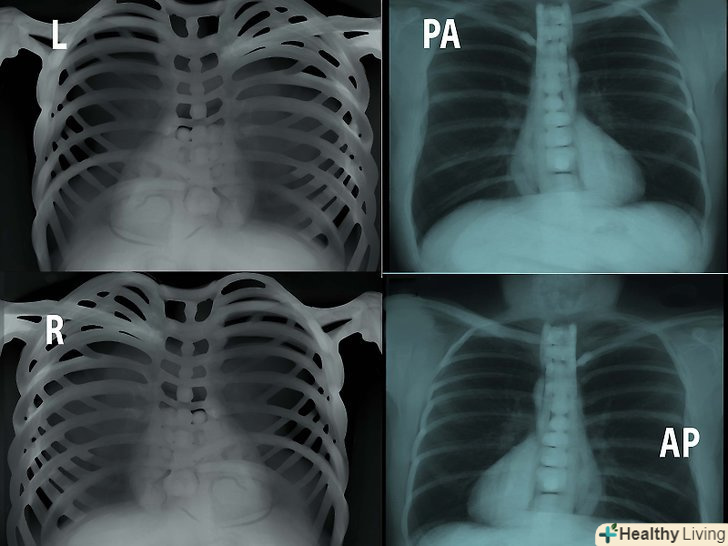

Врахуйте тип знімка (стаття про флюорограми, але і те ж стосується і всіх інших знімків). Так, для флюорограми характерно:- Стандартний вид грудей пацієнта-це т.зв. "pa chest", пряма задня проекція, коли рентгенівські промені йдуть від спини до грудей. Такі знімки робляться на вдиху з відстані приблизно 2 метрів.

- Передньо-задня проекція. Тут промені йдуть від грудей до спини. Так роблять знімки маленьких дітей, а також пацієнтів, не здатних стояти. Такі знімки роблять з більш близької дистанції, що пояснюється меншою потужністю апаратів, що дозволяють робити знімки в такій проекції. Як наслідок, AP-знімки, якщо порівнювати з pa-знімками, виглядають більш збільшеними і менш чіткими.

- Латеральна проекція. Промені йдуть від лівого боку пацієнта (що серце на знімку вийшло чіткіше) до правого. Такі знімки також робляться з відстані в 2 метри.

Подивіться на маркери. L-ліво, R-право, PA-задньо-передня проекція, AP-передньо-задня і т.д. зверніть увагу на те, в якому положенні був зроблений знімок.